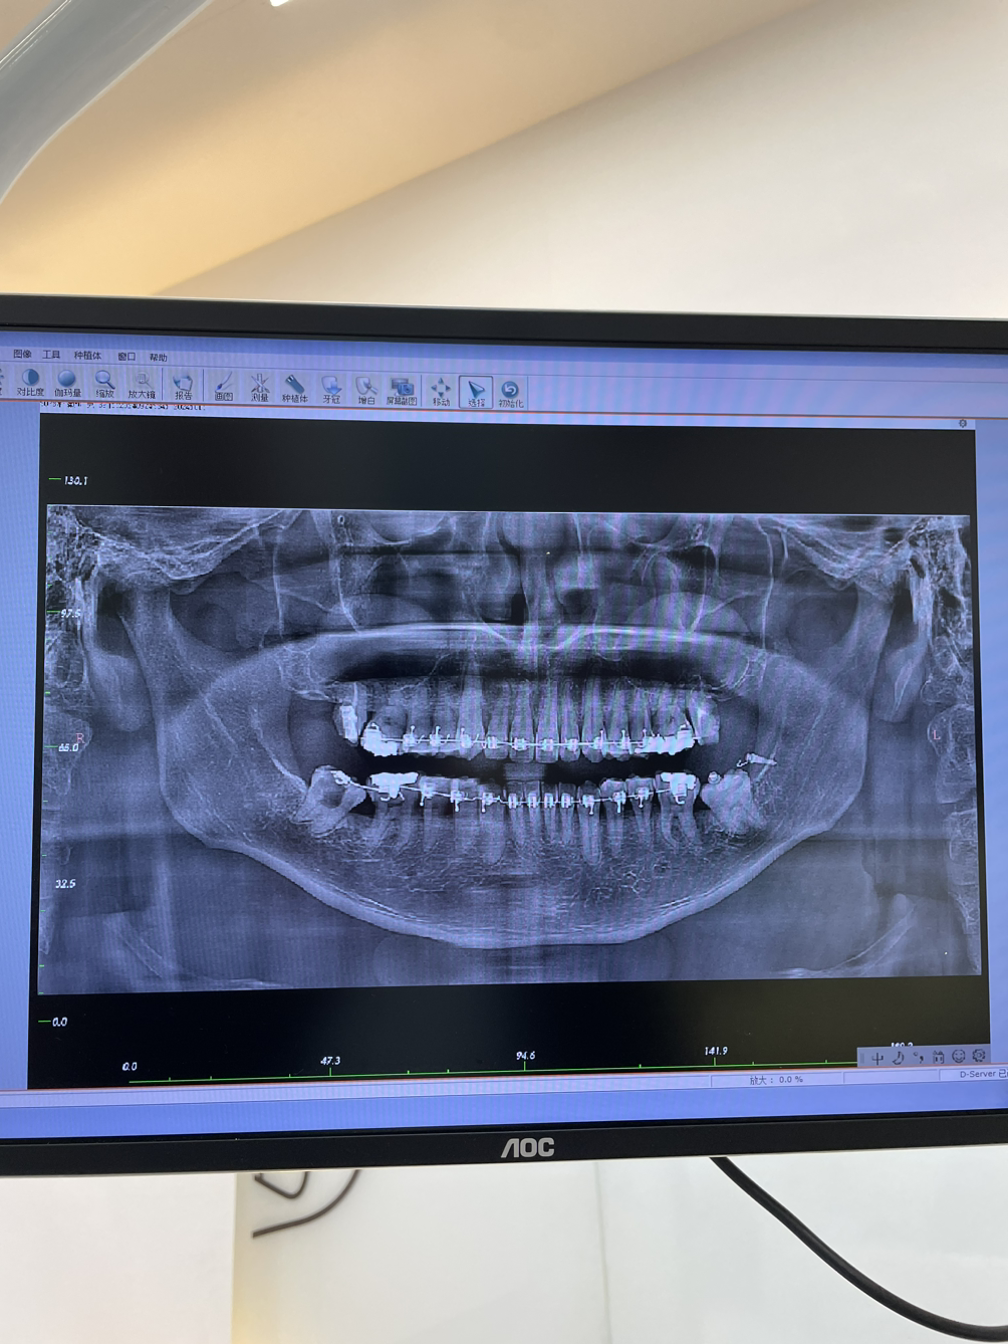

2021년 1월과 2024년 10월, 오른쪽 어금니 임플란트 결정

친절함과 간절함이 만난 결과, 현재 내 어금니는 신경치료가 시급한 상태로 교정을 하고 있다.

교정을 하면 발치를 하고 임플란트를 할 수도 있는 상황,

여러 가지 고민 끝에 그냥 발치하기로 결정했다.

다른 치아는 교정을 거의 마쳤다는 사실에 위안을 받으며, 결정했다.